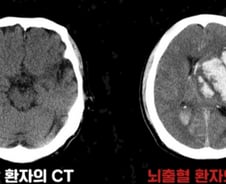

뇌에 갑작스럽게 타격이 가해지는 질환이 뇌졸중이다. 뇌졸중은 △뇌혈관이 막히는 '뇌경색' △혈관이 터지는 '뇌출혈'(출혈성 뇌졸중)로 나뉜다. 이 가운데 뇌출혈은 전체 뇌졸중의 약 20%를 차지한다. 뇌출혈은 전조 증상 없이 갑작스럽게 찾아오고 예후가 매우 나쁘다. 한번 발병하면 치료하더라도 후유증을 남길 수 있다. 빠른 인지·대처가 생명과 후유증을 좌우한다. 가천대 길병원 신경외과 김명진 교수는 "뇌출혈은 발병 즉시 치료해야 후유증을 남기지 않는다"고 설명했다. 뇌출혈의 가장 큰 원인은 '고혈압'이다. 혈압이 자연스럽게 오르내리는 정상 혈압과 달리, 고혈압은 혈관 벽에 지속해서 부담을 가해 손상을 입힌다. 이렇게 손상된 혈관은 점차 딱딱해지고, 신축성을 잃는다. 이 상태에서 순간적으로 혈압이 빠르게 상승하면 결국 혈관이 터지며 뇌출혈로 이어진다. 고혈압 외에도 혈관 일부가 꽈리처럼 부풀며 쉽게 파열되는 뇌동맥류, 선천적으로 혈관 구조가 비정상적인 뇌혈관 기형, 외상, 출혈성 질환,